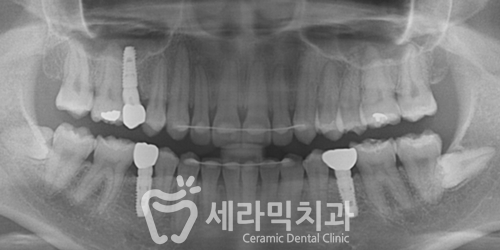

1,2,3번 자리 3군데에 임플란트를 식립하였습니다.(아래 사진)

돌출된 앞니, 나비치아가 깔끔하게 개선되었으며

유치가 있던 자리, 영구치가 나지 못하고 비어있던 자리는

임플란트를 통해 수복하면서 치아가 가지런해졌습니다.